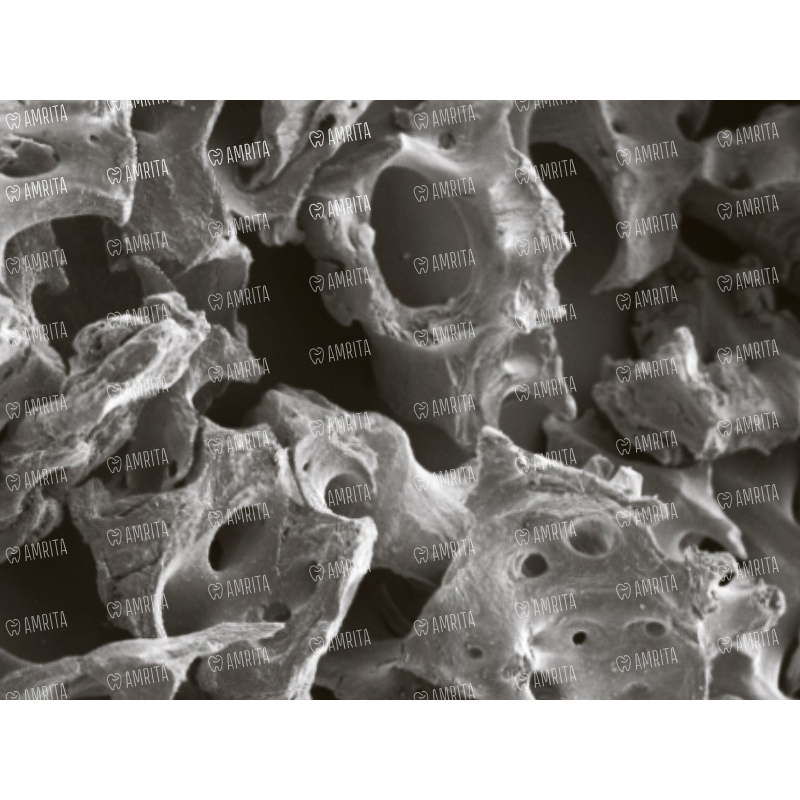

Костный материал XENOGRAFT Mineral — это высокоочищенный биоматериал, состоящий на 100% из минерального компонента губчатой кости бычьего происхождения. Полностью лишенный коллагена, он представляет собой чистый остеокондуктивный каркас для предсказуемой и надежной регенерации костной ткани.

• Чистый остеокондуктивный каркас. XENOGRAFT Mineral служит высокоэффективной матрицей, по которой мигрируют остеобласты пациента, формируя новую, полноценную кость. Его структура, идентичная человеческой губчатой кости, создает идеальные условия для прорастания сосудов и регенерации.